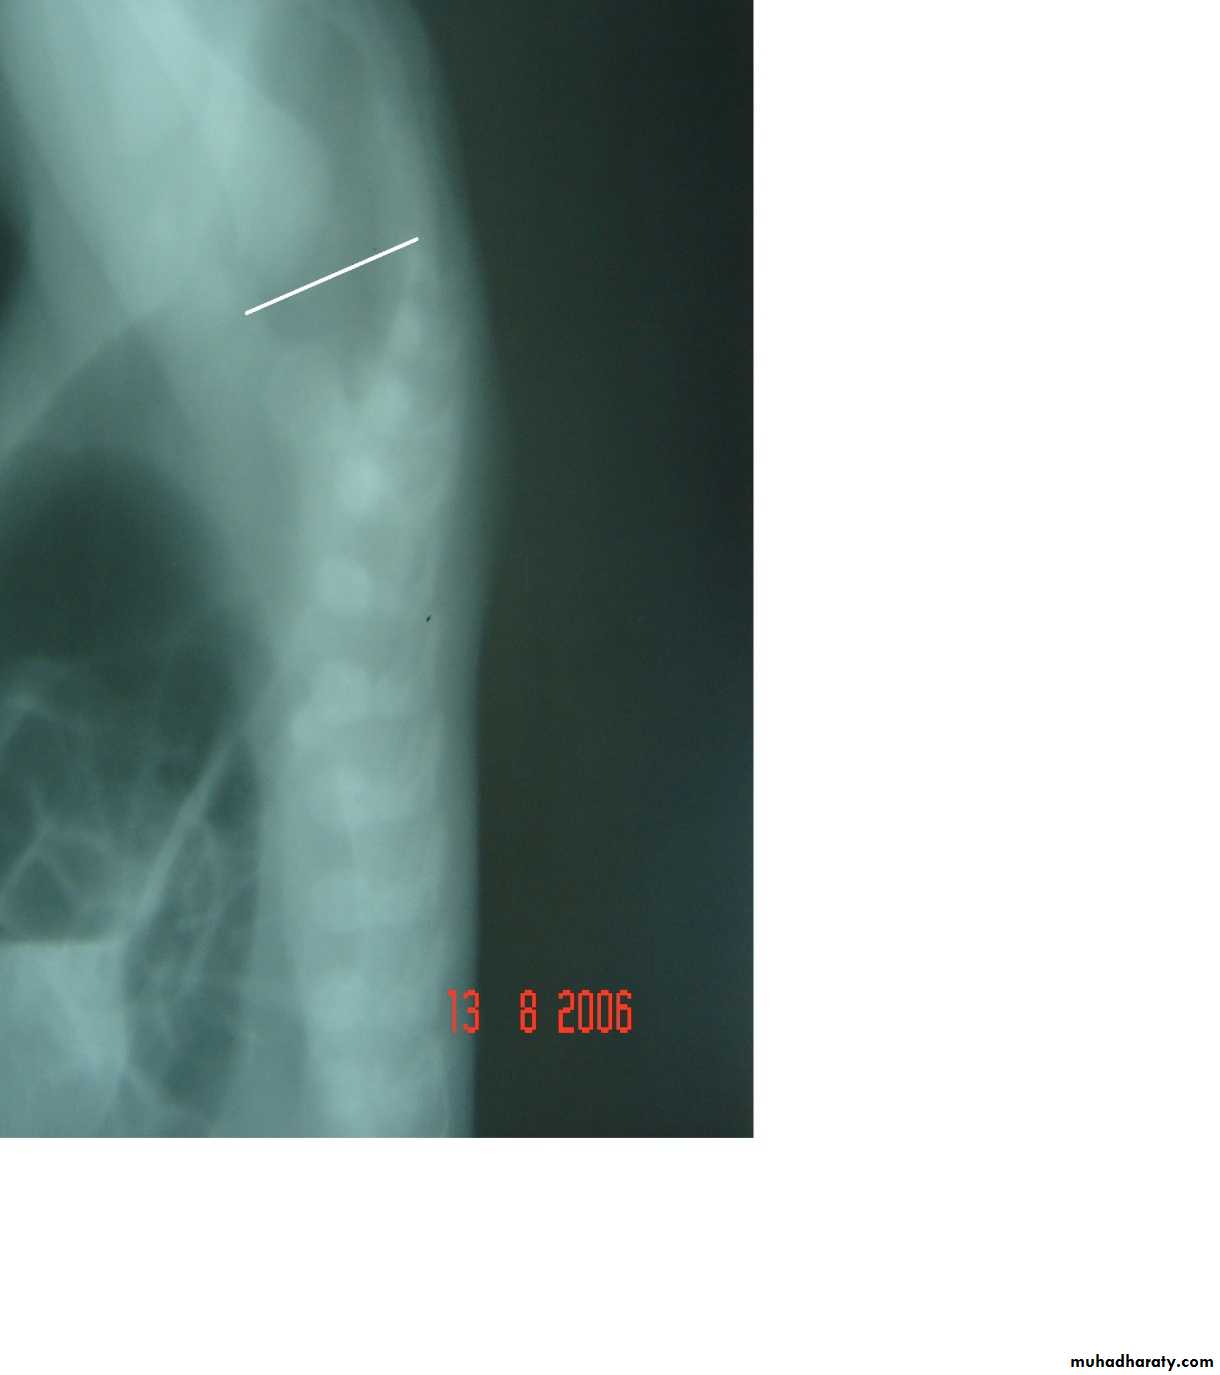

Oesophageal Atresia and Tracheo-Oesophageal Fistula,